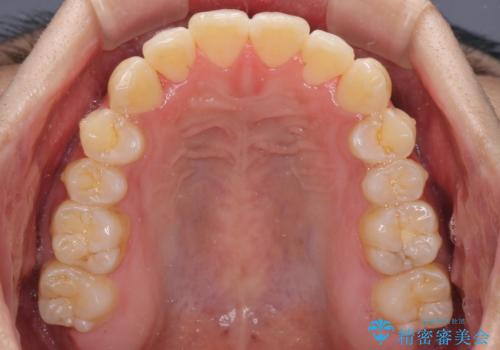

全体的に軽微な叢生が認められ、口元もやや前方に突出していたため、インビザラインでのIPR(歯と歯の間を削る)と歯列全体の後方移動によって歯並びを整えることとしました。

上下ともに歯列の幅が狭かったため、側方に拡大することで前歯のデコボコや突出感を解消するためのスペースを獲得することができました。